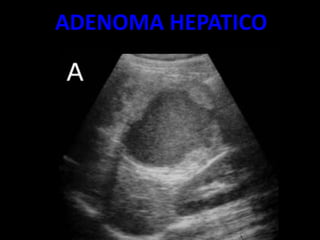

ADENOMA HEPATICO

• SUELEN SER LESIONES

REDONDEADAS

• SÓLIDAS GENERALMENTE ÚNICAS

• BIEN DELIMITADAS.

• OSCILA ENTRE 6 A 15 CM